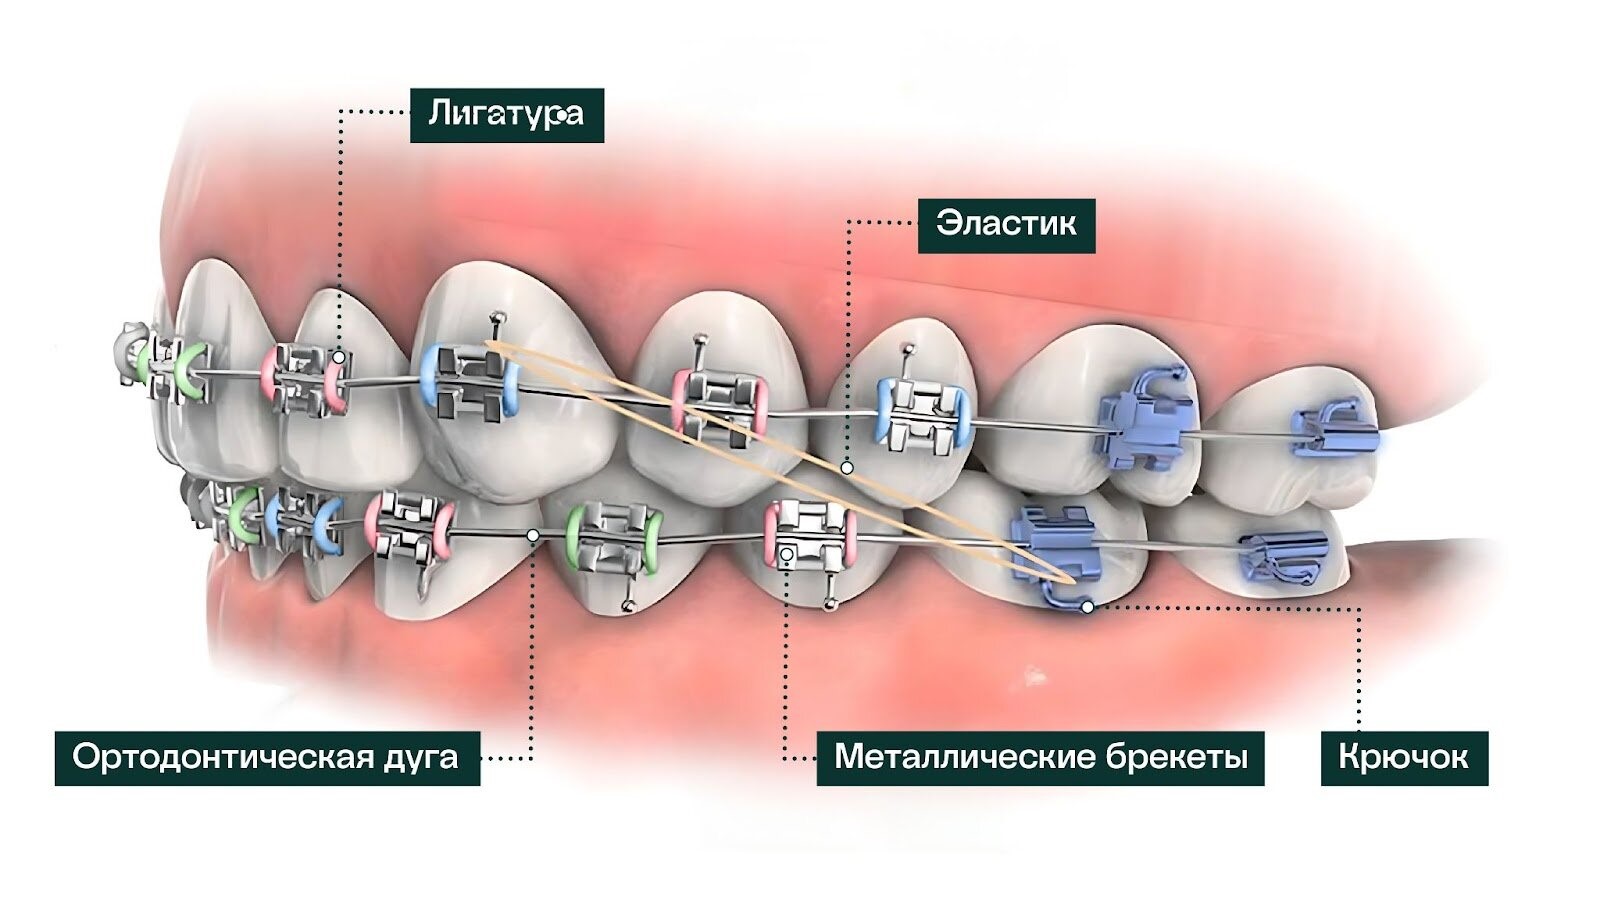

Правильный прикус — важная составляющая голливудской улыбки. Нарушения прикуса встречаются у большинства людей и могут варьироваться от незначительных до серьезных. Для исправления прикуса может потребоваться консультация ортодонта. Врач предложит оптимальное лечение — прозрачные каппы или брекеты, в зависимости от сложности случая. Каппы (элайнеры) — удобный метод коррекции прикуса. Их нужно носить ежедневно, снимая только на короткое время для еды и чистки зубов. Каппы постепенно сдвигают зубы в правильное положение, и их нужно менять по мере продвижения лечения. Преимущество капп в том, что их можно менять самостоятельно, не посещая стоматолога ежемесячно.

Брекет-системы— эффективное средство для исправления сложных случаев неправильного прикуса. Современные брекеты изготавливаются из металла, керамики или сапфира, что делает их менее заметными. А лингвальные брекеты крепятся на внутреннюю поверхность зубов и остаются невидимыми.

Сделать красивые зубы в Москве — сколько это стоит

Врач-стоматолог при составлении плана лечения обсуждает с пациентом бюджет и финансовые возможности. Ортодонт подберет брекет-систему: цена полного курса на начинается от 100 тысяч рублей, или элайнеры (от 200 тысяч). Установка 1 цельнокерамического винира — от 30 000 рублей.